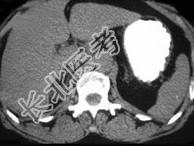

- 单项选择题女,35岁, 无意中发现血压高,实验室检查: 血和尿中醛固酮水平增高,请结合所提供图像, 作出诊断 ( )

A、右肾上腺增生

B、右肾上腺Cushing腺瘤

C、右肾上腺皮质腺瘤

D、右肾上腺转移瘤

E、右肾上腺囊肿